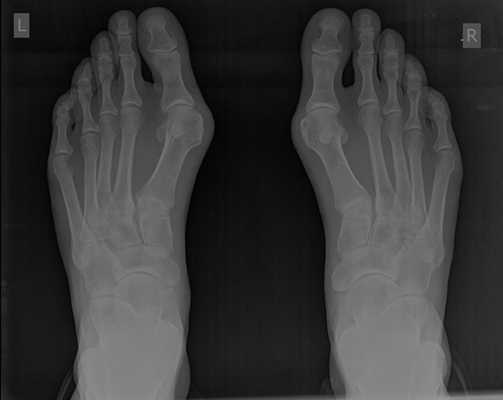

При планировании оперативного пособия выполняются рентгенограммы в прямой и боковой проекции. Производится расчёт углов вальгусного отклонения 1 пальца, угол между 1 и 2 плюсневыми костями, угол артикуляции 1 плюсневой кости. Исходя из рассчитанных углов, выбирается оптимальный метод остеотомии для коррекции имеющейся деформации.